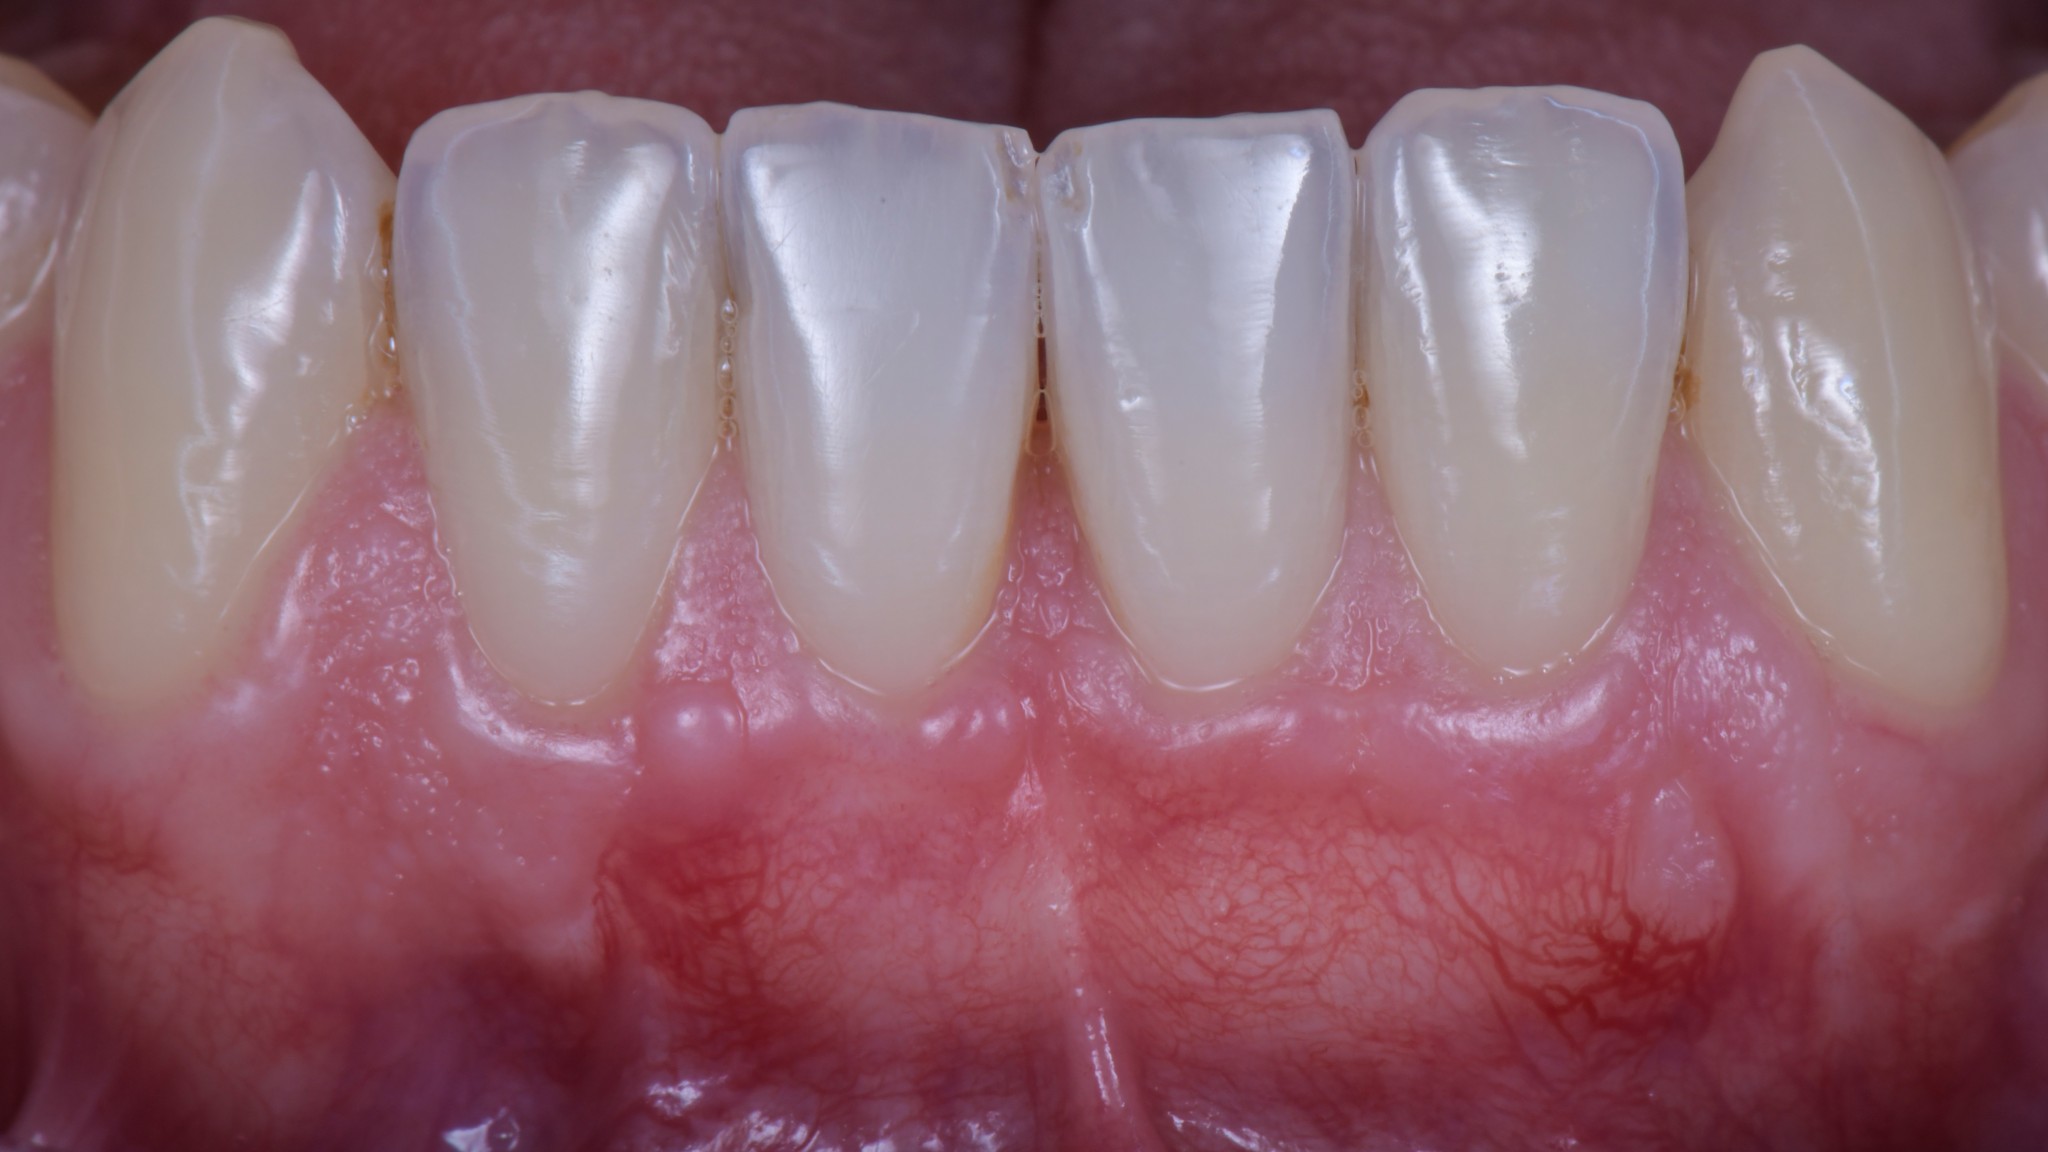

Guarda che bel caso:

Osserva attentamente dove sono le inserzioni muscolari e dove attacca il frenulo. Dicevamo che la zona più merdosa è proprio il quinto sestante perché la mucosa è sempre estremamente sottile ed è l’unico settore anatomico dove c’è un muscolo vero coi controcazzi. Il muscolo mentale.

Ma soprattutto di arrivare a 3 mesi in questa:

Nonostante lo spostamento coronale di circa 5 mm le inserzioni muscolari e il frenulo sono esattamente nella stessa posizione di prima. Il fatto che ci sia uno slivellamento della linea mucogengivale è un’ovvia conseguenza dell’intervento, quella non la possiamo evitare, ma ci penserà la Natura. Ancora qualche mese e tutto tornerà a posto da solo.

Non si vede bene?!

Hai ragione. Ti faccio un’altra foto:

Le vedi adesso le inserzioni? ?